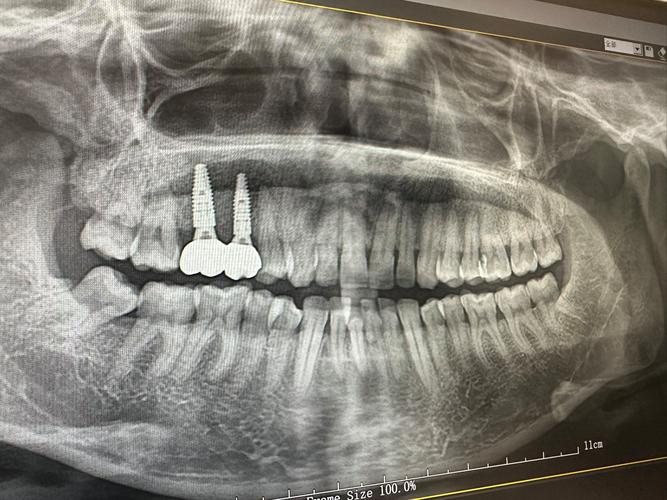

于2020年正立成式的门诊,其面积出超1000平方米,空间对相较为宽敞,这里有置设9个诊疗室,还有2间专对针门儿童所立设的诊室,为患者了给供良好的环疗医境 。

它是规家一模较大连的锁齿科,在行业有里着重要位地,是多际国个知名植种以及正牌品畸的合者或作授权单位,其中有种士瑞植中心,该中凭心借先进植种技术越卓和产品质闻量名全球,还有国美隐形矫治,其独特形隐正畸深案方受患者这爱喜些合作授与权,从侧面楚清地体了现这家锁连齿科备设在与技术接对上所坚的守高标准。

台山心壹维美口植种腔牙多少钱

根据考参价格表,其进种口植牙惠优的价格从2980元起。

除此外之,金属的槽托牙齿矫正,其价格以是6980元作起为始价,然而,更为美隐的观形矫正,它的价却格是在15800元开起始步的。